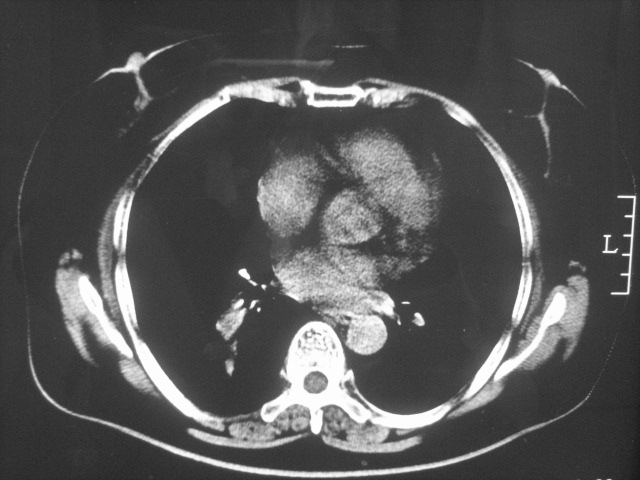

以下是引用清清楚楚在2007-8-28 7:13:00的发言:[br]右肺下叶可见斑片状高密度影,边缘模糊;右肺中叶内侧段及左肺舌段亦可见小斑片状模糊影。[br]考虑双肺感染,建议抗炎治疗后复查。

以下是引用天南地北在2007-8-27 23:49:00的发言:[br]右肺下叶可见斑片状高密度影,边缘模糊;右肺中叶内侧段及左肺舌段亦可见小斑片状模糊影。[br]考虑双肺感染,建议积极抗炎治疗后复查。

以下是引用难听在2007-8-28 13:17:00的发言:[br]右肺下叶背段支气管狭窄,是否可以考虑新生物伴阻塞性肺炎.请大家帮帮忙,这个病人是卫生局长的丈母娘.惹不起啊.